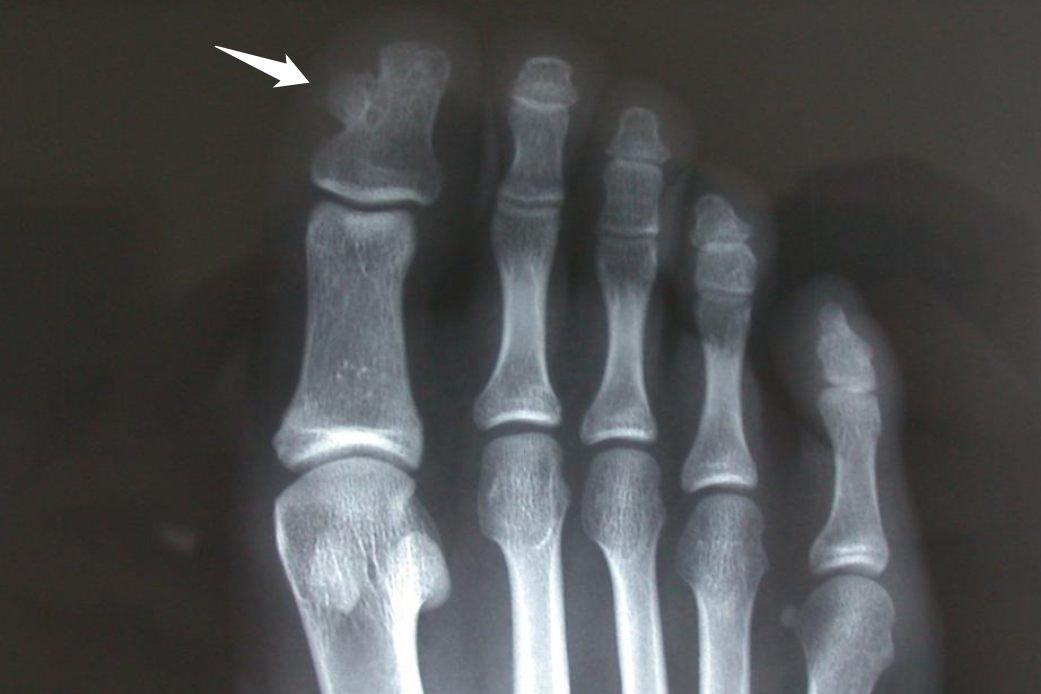

外生骨疣通常由致密骨质构成,常发生于骨表面;内生骨疣是发生于骨髓腔内的骨瘤。

外生骨疣是多发于长骨干骺端,生长于关节周围,是正常骨骼上的骨性隆起,为无痛性的、质硬的包块。当包块压迫周围软组织时,可引起患处关节疼痛和酸胀不适,并可导致滑膜炎。

内生骨疣在体表通常无表现,主要是位于骨髓腔内包含在正常组织中的异常片块状骨岛,由成熟板层骨构成。患者通常无明显自觉症状,患处无疼痛。